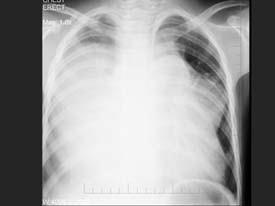

问题 男,13岁,胸痛胸闷2月,胸部检查如图,最可能的诊断为 ( )

选项 A、先天性心脏病,动脉导管未闭 B、右侧胸腔大量积液 C、纵隔占位 D、先天性心脏病,房缺 E、心力衰竭并右侧胸腔积液

答案 C